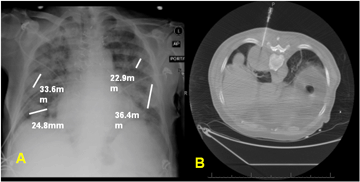

The patient did well during follow-up until 1999, when he was admitted for fatigue, weight loss and shortness of breath and was found to have lymphadenopathy. Subsequent imaging, blood analysis and biopsy confirmed the diagnosis of stage IV non-Hodgkin's lymphoma. He was then treated with CHOP systemic chemotherapy and went into remission. In March 2011, he presented to our emergency department with acute shortness of breath and a workup revealed acute mitral regurgitation as the underlying cause. During his stay at our facility, multiple pulmonary nodules were discovered on chest radiogram (Figure 1) and computed tomography (CT) scan showed multiple multilobar lung masses, measuring up to 8.4 cm x 5.3 cm. Magnetic resonance imaging (MRI) of the brain showed recurrent versus residual meningioma (Figure 2)– however this was not further biopsied. A left upper lobe nodule fine-needle aspiration revealed metastatic malignant meningioma via light microscopy (Figure 3) and immunohistochemistry staining (Figure 4). A surgical resection was indicated because of the doubling of one of the lung masses (RLL nodule from 3 cm x 3 cm to 3 cm x 6 cm in less than twelve months), in order to confirm the diagnosis. Again, metastatic malignant meningioma was confirmed by biopsy. PET scan showed multiple hypermetabolic lesions throughout the lung. Unfortunately, soon after, the patient deteriorated after developing mitral valve endocarditis and died from multi-system organ failure.

Figure 1: (A) Chest roentgenogram shows multiple pulmonary nodules, two in the right and two in the left lung lobes (marked off with measurements), (B) The chest computed tomography showing multilobar lung masses during a CT-guided fine needle aspiration of a right posteriomedial pleural mass.